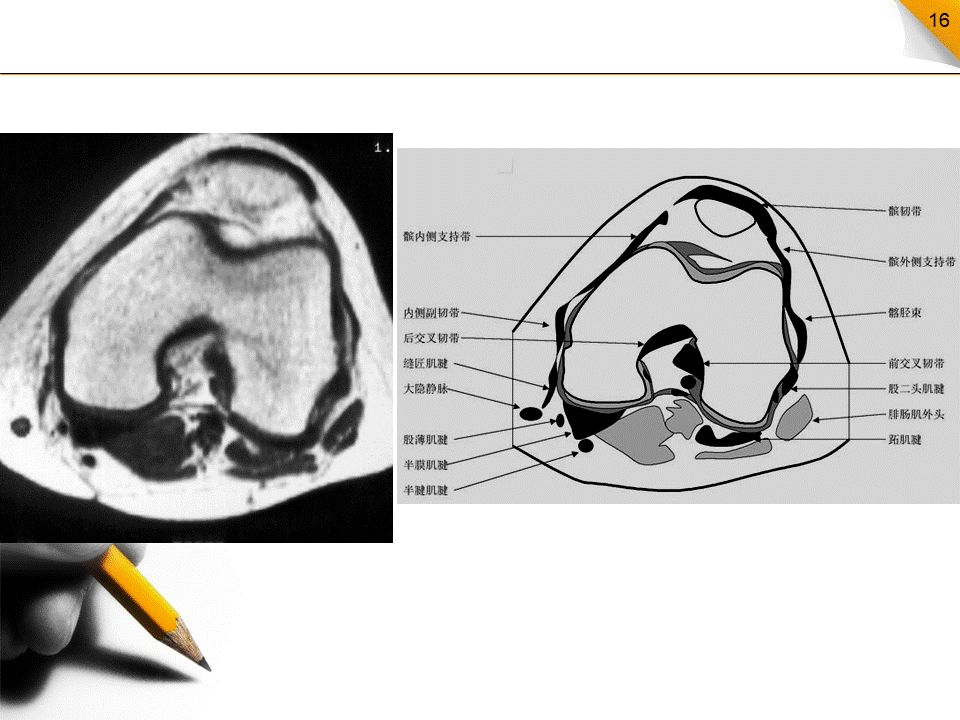

膝关节MR解剖(横断面)

是三维影像首选的方位,也是为了便于MRI与CT比较可准确地展现髌骨内外侧关节面